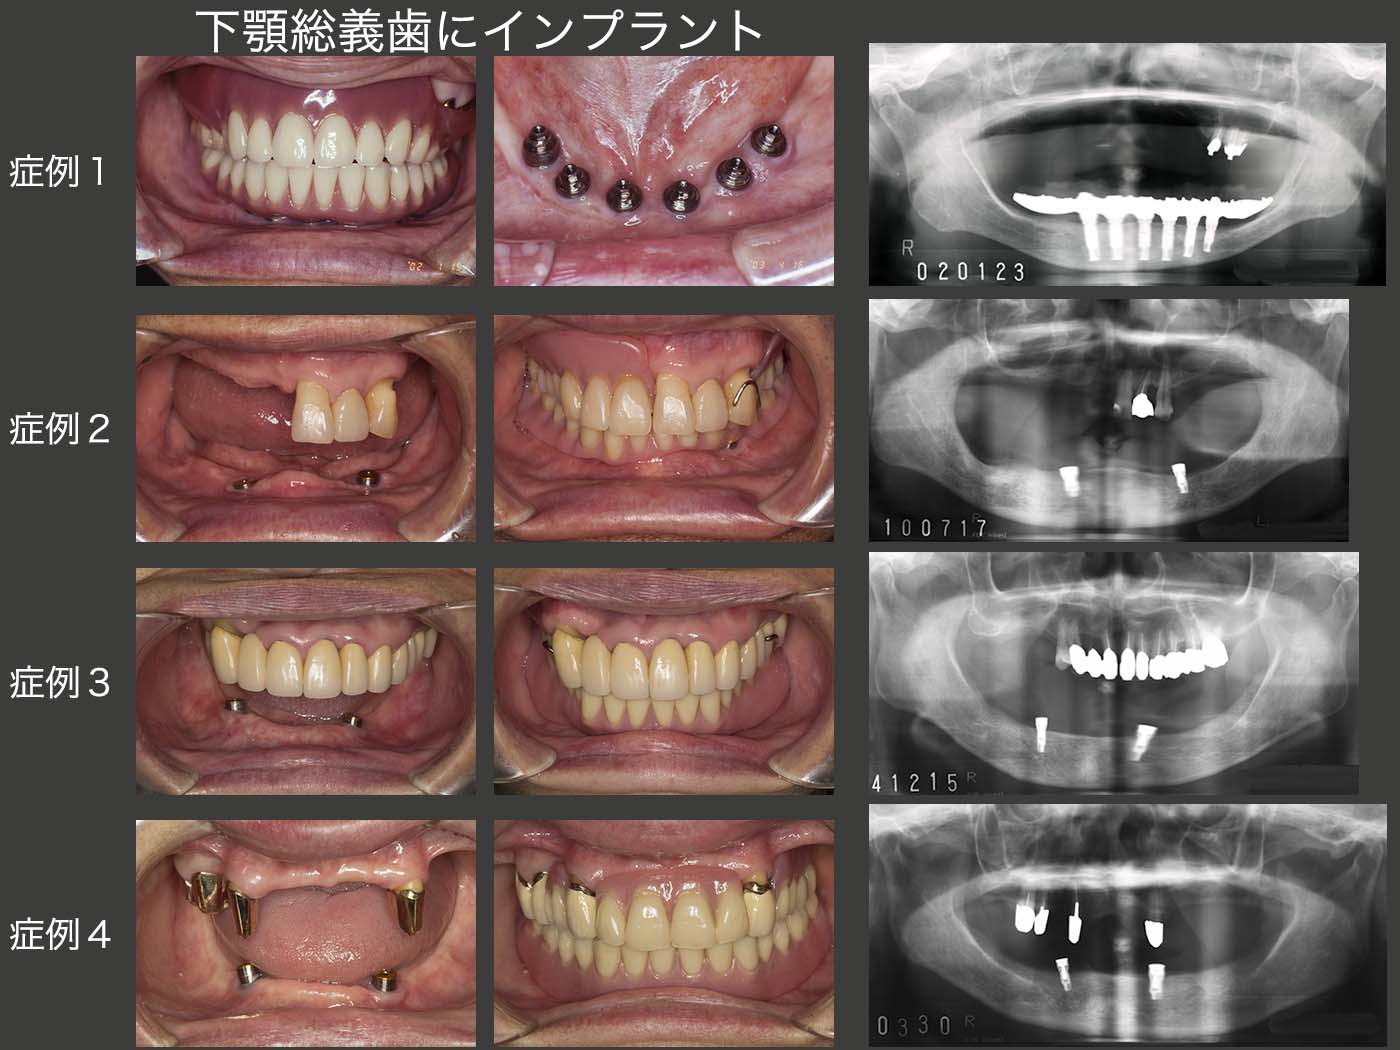

7.下顎総義歯にインプラント

上顎の総義歯は顎堤がある程度あれば義歯で十分対応できるが,さらに補綴装置の安定,装着感の改善を求めてインプラントを植立することも稀にある.しかし,将来インプラントに感染が生じた場合は,顎堤吸収を助長してしまう.特に長いインプラントを用いる場合は,顎堤の吸収が大きく,次に総義歯を製作するときに難症例に陥る危険性がある.すなわち,基本的には上顎にインプラントを用いる必要はない.どうしても口蓋の違和感,あるいは発音障害の強い人は,将来危険があることを良く承知したうえで,最小限のインプラントを用いるべきであろう.

下顎の総義歯も,上顎と考え方は同じである.しかし,下顎の顎堤のない症例に安定した総義歯を製作できる歯科医師は少ないであろう.私も自信がない.インプラントを使用できれば遥かに安定した義歯を製作できる.但し,上顎と同じで,感染が生じて撤去するような事態が生じた場合,その後に製作する義歯がさらに難症例になってしまうということは肝に銘じている.

症例1は,2002年に下顎に6本のインプラントを埋入した症例である.当時は,6本がスタンダードであった.これは,特に欧米人が固定式の補綴装置を望むことが影響しているのであろう.なお今現在,18年経過するが,特にインプラントに問題は生じていない.しかし,上顎の顎堤の吸収量が通常より多いような気がする.

その後,可撤式の義歯を用いる場合は少ないインプラントでも術後経過が良いことが分かってきた.そこで私も,可撤式の義歯にしていただき,最小限2本のインプラントを用いるようになった.(症例2〜4) 但しこの場合も,なるべく短いインプラントを用いて,もし感染が生じた場合,顎堤の吸収が最小限の被害ですむように心掛けている.

なお,症例4の右下のインプラント(15年装着)が20年10月に脱落してしまった.